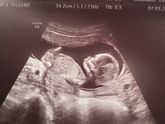

7 марта 2020 10:43 Были с мужем на УЗИ , сказала пол ребёнка девочка??????? Ну я так хотела мальчика ??